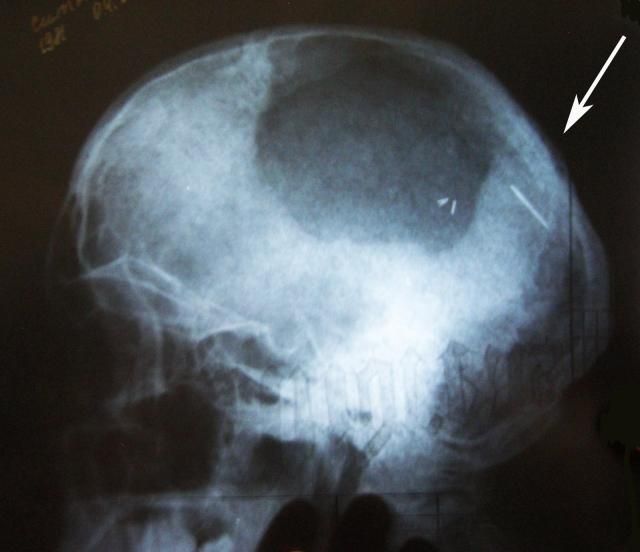

Женщина узнала об игле в головном мозге после обследования. Накануне китаянка просто потеряла сознание на работе, поэтому и обратилась к медикам. Уже они рассказали о находке в голове пациентки.

Сама пациентка не знает, как игла могла попасть ей в голову. Врачи предположили, что это могло случиться ещё в раннем детстве.